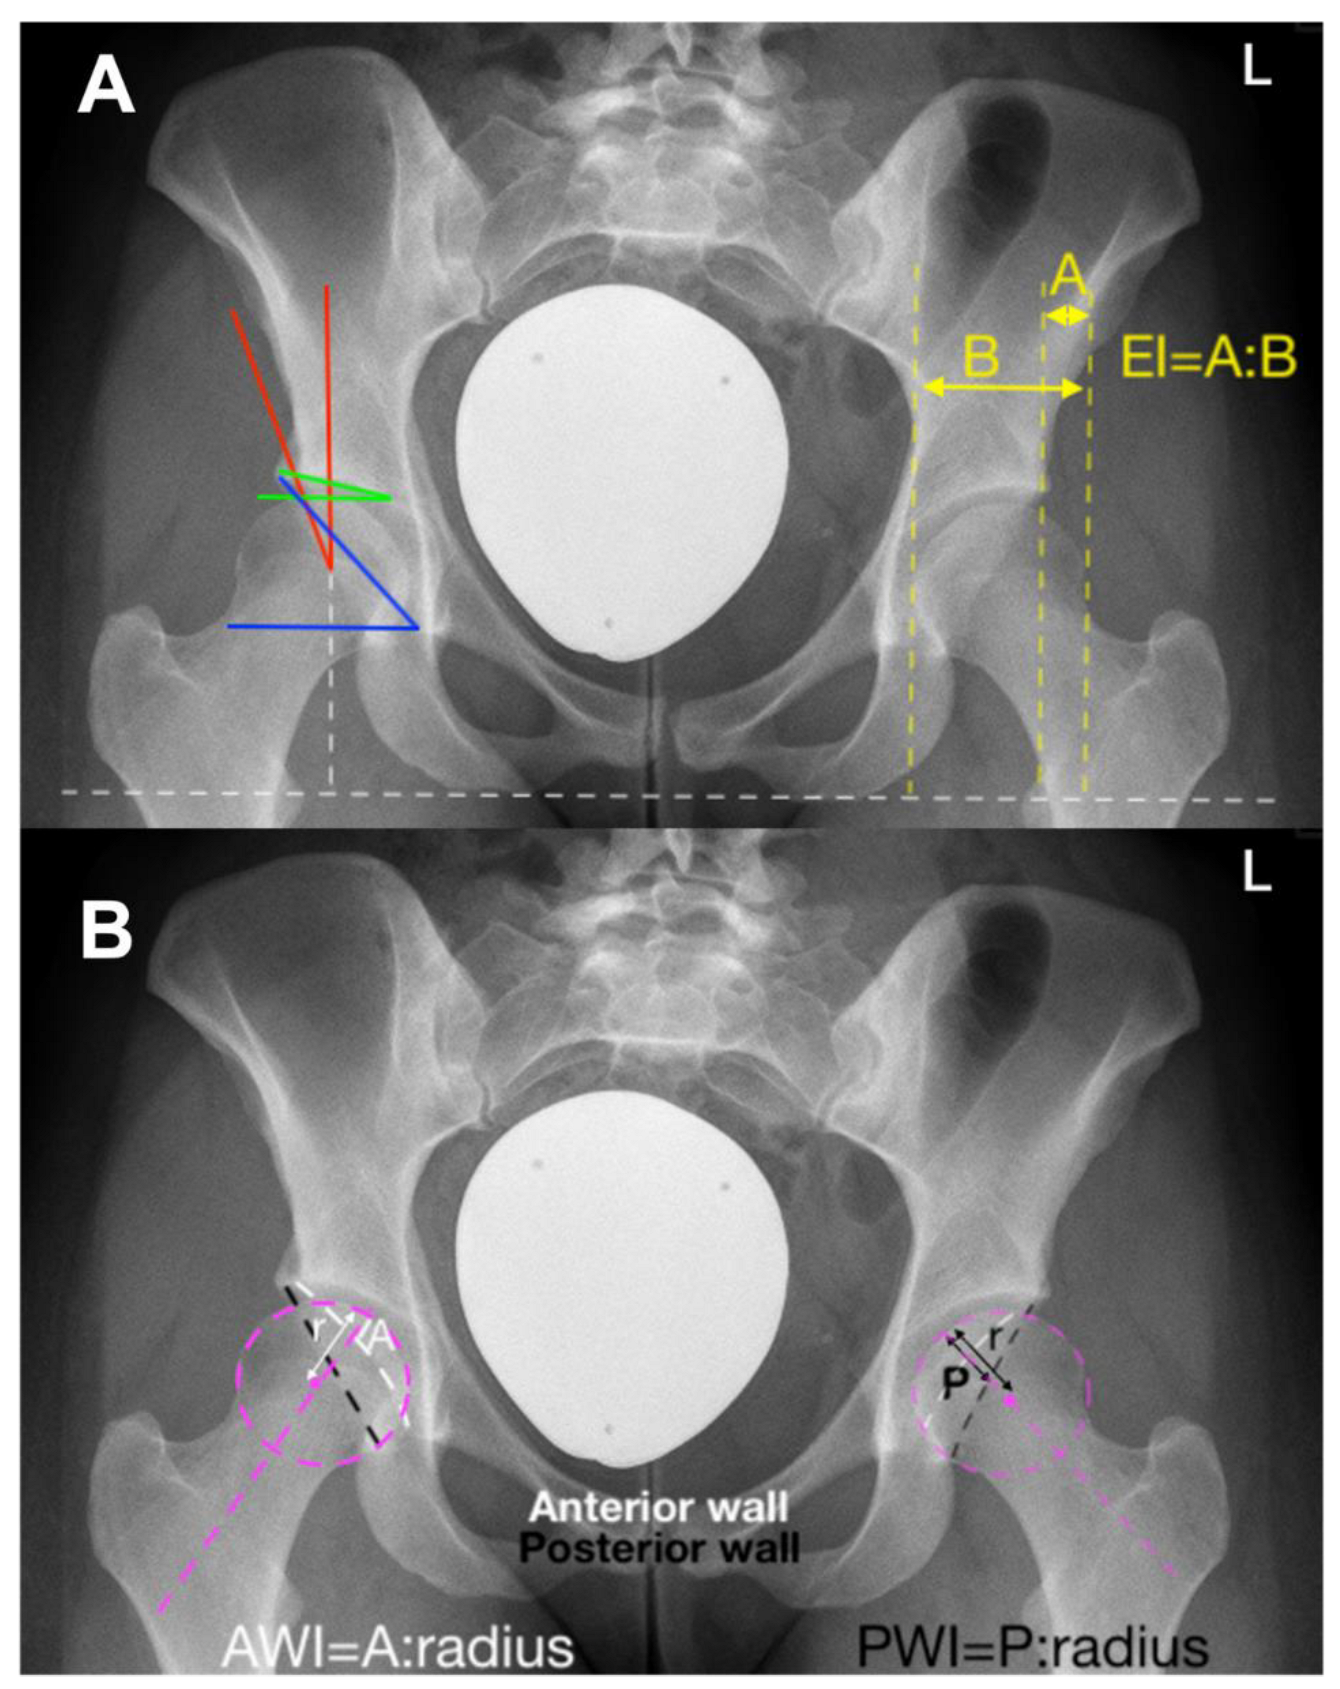

- − Lateral center edge angle (LCEA): 22°

- − Acetabular index: >14°

- − Extrusion index: >27%

- − Anterior wall coverage: <14%

- − Posterior wall coverage: <35%

- Stetzelberger, V.M.; Leibold, C.S.; Steppacher, S.D.; Schwab, J.M.; Siebenrock, K.A.; Tannast, M. The Acetabular Wall Index Is Associated with Long-term Conversion to THA after PAO. Clin. Orthop. Relat. Res. 2021, 479, 1052–1065. [Google Scholar] [CrossRef] [PubMed]